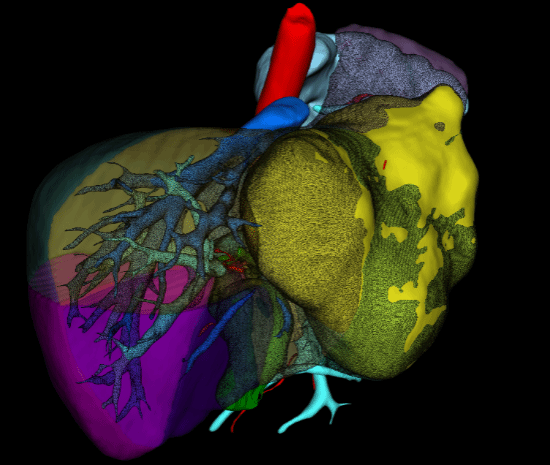

抗休克同时,蒋安主任医师团队完善必要的术前检查:患者Child A级肝功,ICGR15 <10。经肝脏三维重建模拟计算后发现:肝肿瘤体积约为888.6cm3,拟切除包含肝中静脉的扩大左半肝体积为1096.3 cm3,,残肝体积1306.6 cm3,,标准肝体积1374.1 cm3,,残肝比达到95%(图3、图4)。经过与曲凯副主任科室讨论后认为,残余肝脏满足安全需求,在患者条件满足一期手术的情况下急诊切除肿瘤,较介入止血更为直接。决定为患者实施切除肝左、肝中静脉的扩大左半肝切除术。